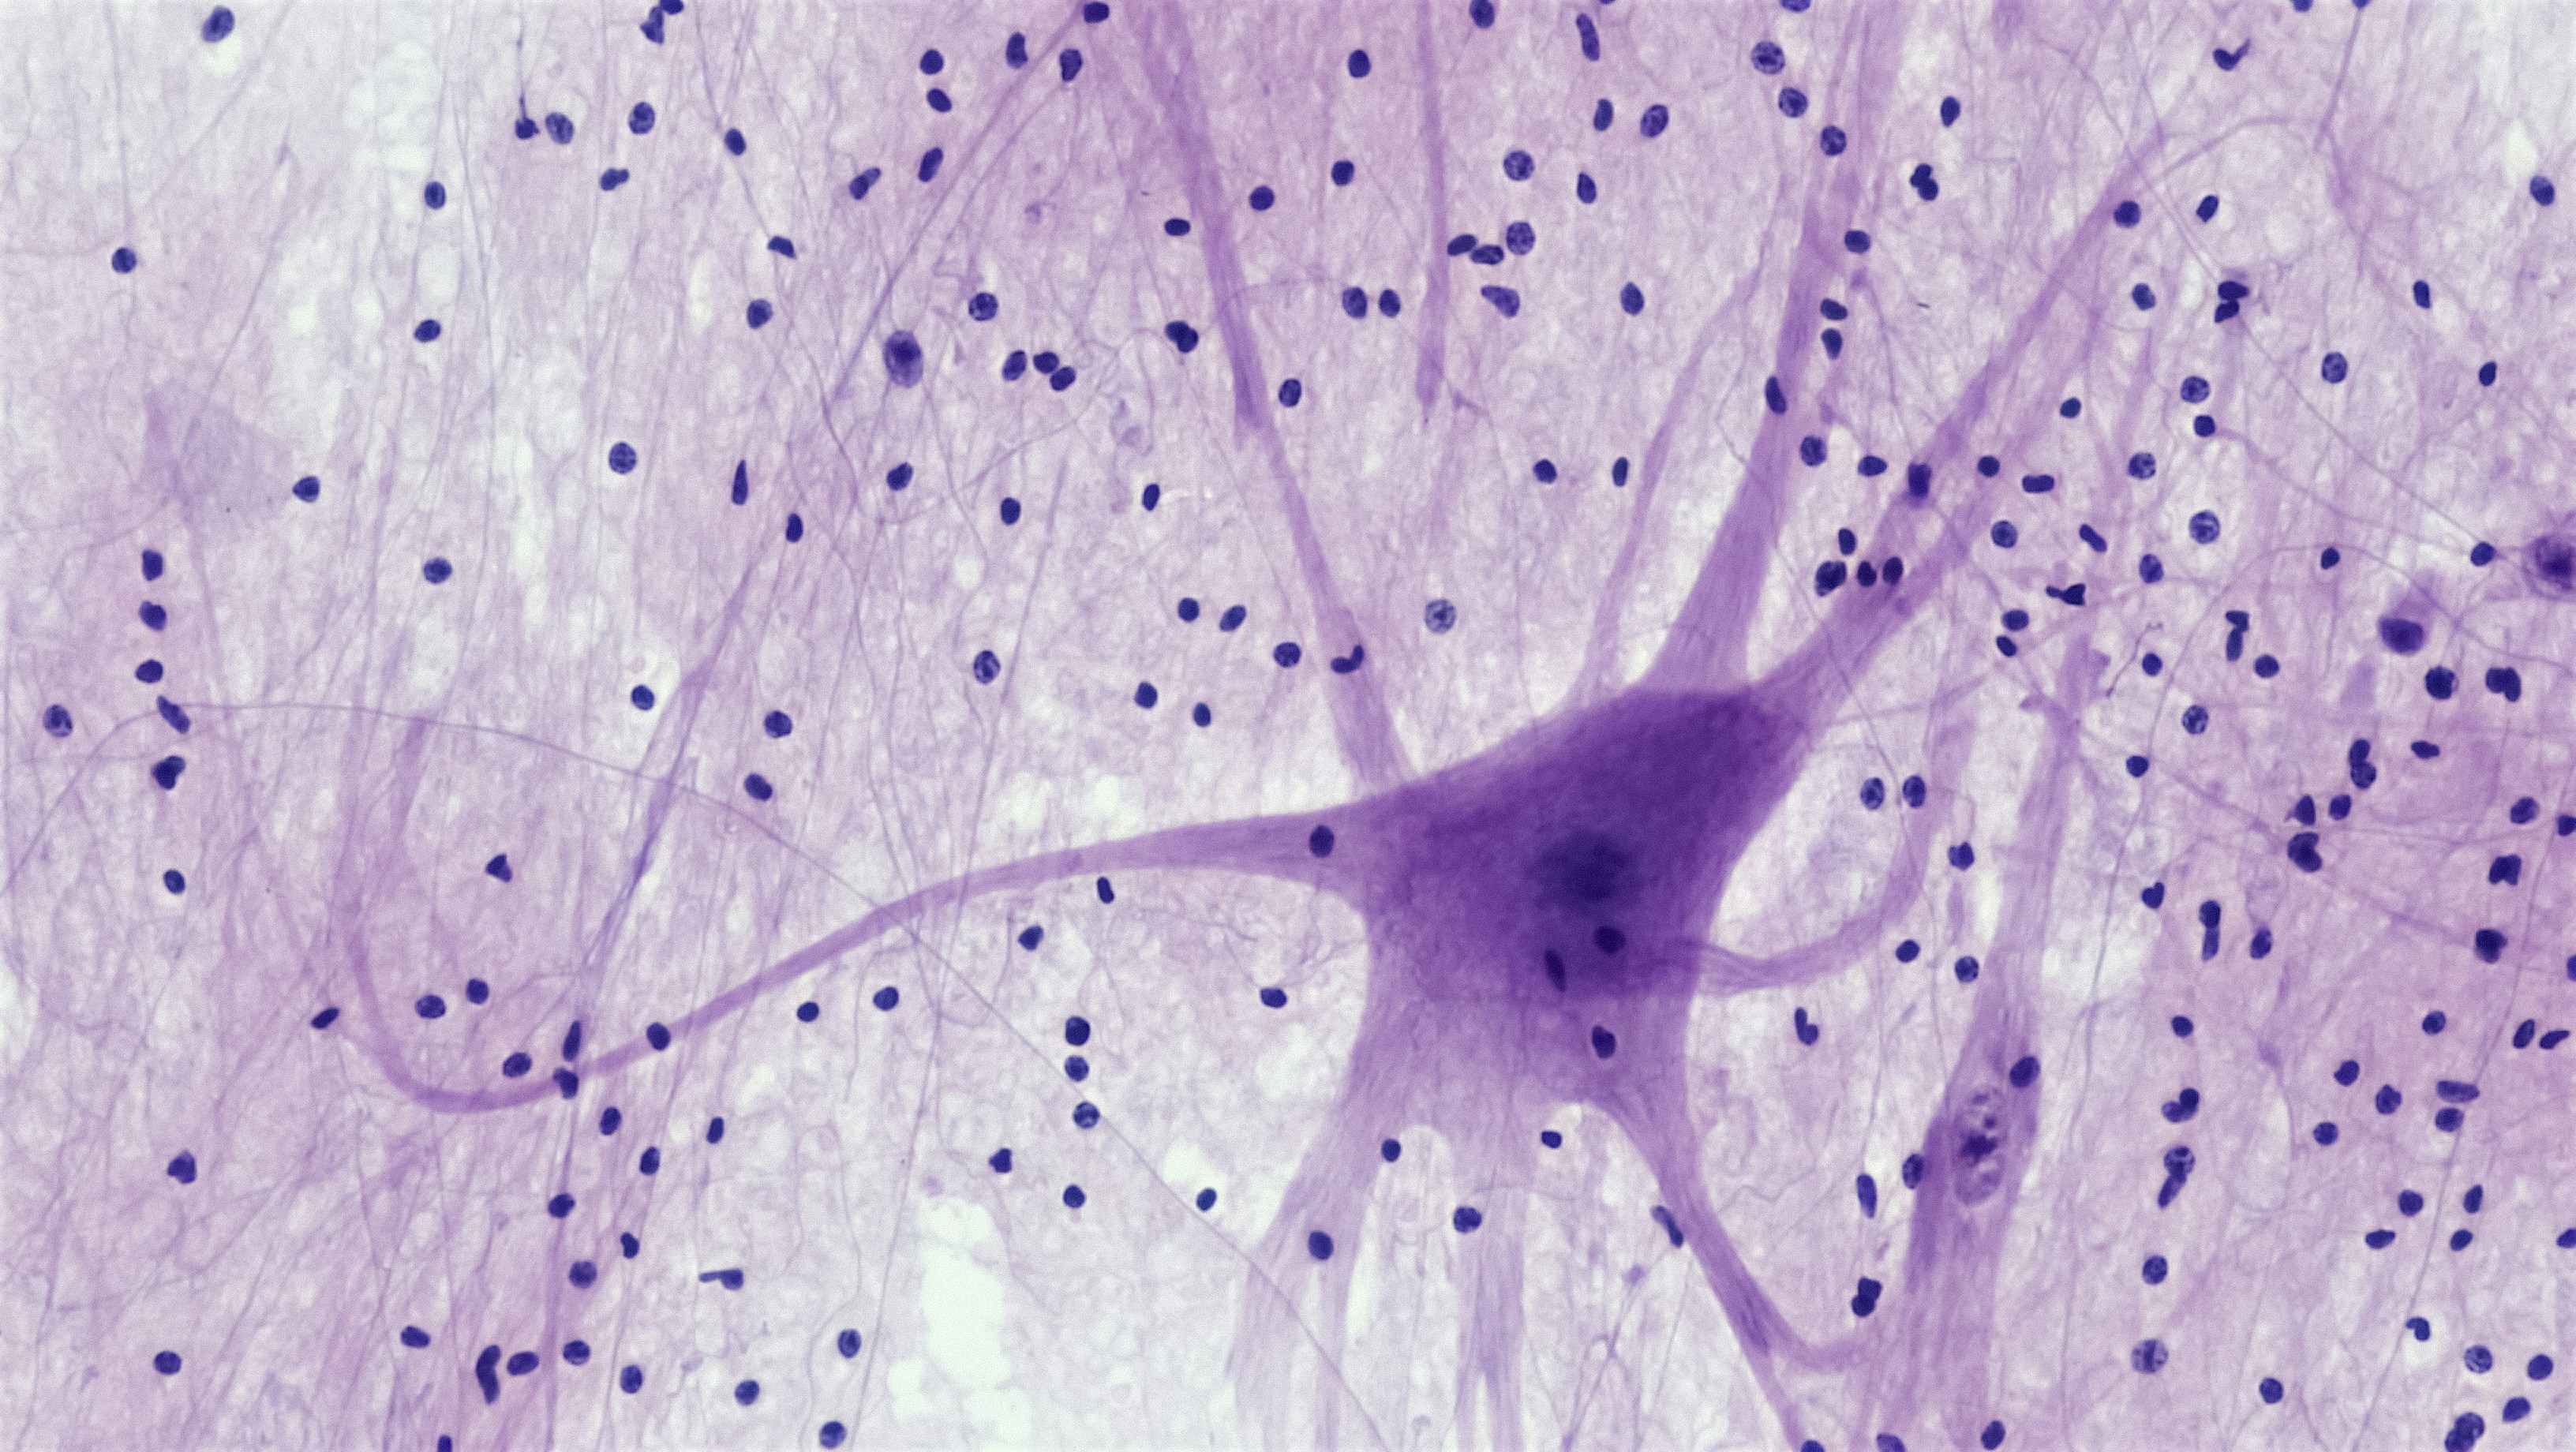

Regularización del espacio latente para mejorar la segmentación de imágenes médicas